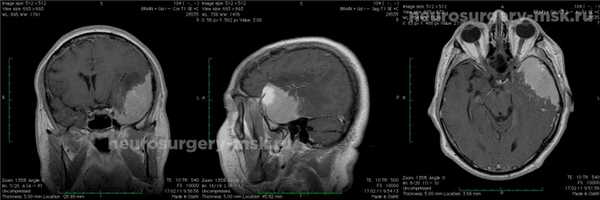

Диагностирование: МРТ, производилось с усилением контрастного типа.

Менингиома средней черепной ямки (до операции)